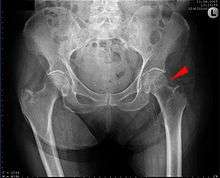

![]() AP hip radiograph demonstrating an intertrochanteric fracture | |

X-rays of the affected hip usually make the diagnosis obvious; AP (anteroposterior) and lateral views should be obtained.

In situations where a hip fracture is suspected but not obvious on x-ray, an MRI is the next test of choice. If an MRI is not available or the patient can not be placed into the scanner a CT may be used as a substitute. MRI sensitivity for radiographically occult fracture is greater than CT. Bone scan is another useful alternative however substantial drawbacks include decreased sensitivity, early false negative results, and decreased conspicuity of findings due to age related metabolic changes in the elderly.